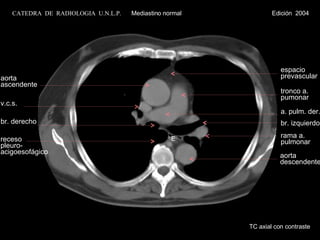

aorta ascendente v.c.s.br. derecho receso pleuro- acigoesofágico rama a. pulmonar tronco a. pumonar a. pulm. der. br. izquierdo aorta descendente espacio prevascular TC axial con contraste E CATEDRA DE RADIOLOGIA U.N.L.P. Mediastino normal Edición 2004

aorta ascendente v.c.s. br. derecho receso pleuro- acigoesofágico rama a. pulmonar tronco a. pumonar a. pulm. der. br. izquierdo aorta descendente espacio prevascular TC axial con contraste E CATEDRA  DE  RADIOLOGIA  U.N.L.P.   Mediastino normal  Edición  2004